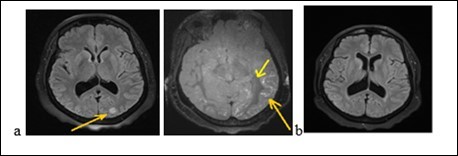

Mrs. A.S., a woman of 56, was admitted to hospital on february 9, 2018 for gradual onset in a three week, confusion, intense and diffuse headache with vomiting and photophobia. She treated the headache in automedication with a non-steroidal anti-inflammatory drug (NSAID, ibuprofen). The symptoms had worsened after 3 weeks with a serious trouble as her environment noted it. She had no story of vascular pathology. The neurological examination noted a neck stiffness, trouble and mutism. On the cardiovascular examination, the blood pressure was of 210/90 mm Hg. The examination of the other organs was normal. The blood count showed a leukocytosis at 12600 / mm3. The serum creatinine, glycemia, thyroid hormones and blood ionogram were normal. The cerebrospinal fluid (CSF) revealed 27cells/mm3 predominantly neutrophilic, with a normal glycorachia and hyperpropteinorachia of 0.6g/l. There was no germ in CSF after the preparations. The initial brain MRI (Figure 2a) had shown a range of edema in the left occipital lobe and diffuse enhancement of the leptomeninges. The electroencephalogram (EEG) had shown some slow waves in the left occipital lobe, with no epileptic figure or encephalopathy. The patient had been treated with nimodipine (60 mg every 8 hours) associated with analgesic drugs. The trouble and headache had decreased. The brain MRI (Figure 2b) at one (1) month had shown a complete decrease of the germs. The clinical and imagery findings fell on diagnosis of RPE syndrome.

Figure 2.Cerebral MRI showing a left occipital edema and a diffuse contrast enhancement of the leptomeninges (a) with complete decrease of the lesions after treatment (b)